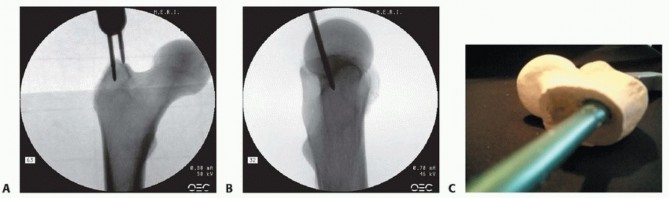

C. Percutaneous joystick eccentrically placed to allow passage of reducer. D. Percutaneous joystick and percutaneous bone hook. E. Open reduction Watson-Jones with two clamps for irreducible high-energy hip fracture. F. Open reduction AP radiograph. G. Open reduction lateral radiograph. H,I. AP and lateral radiographs showing final result. 1. ## Precision Portal Placement and Trajectory Control The rationale for the minimally invasive cephalomedullary surgical technique is based on three concepts to maximize bone and soft tissue conservation during nail implantation and to minimize the potential for malalignment 21: Precision portal placement Trajectory control Portal preservation A precise starting point is the first criterion in ensuring an accurate reduction of proximal fractures, whether the entry portal is a modified trochanteric entry portal or a piriformis portal as defined by the selected nail geometry ( TECH FIG 2A,B).

--- TECH FIG 2 • A. Radiographic position of entry portal. Medial pin is medial trochanteric portal and lateral pin is lateral trochanteric portal. B. Lateral radiographic projection of piriformis portal; trochanteric portals will be aligned to bisect the femoral head more anteriorly. C. Anterolateral trajectory for nail in proximal femur.

(continued)

The proximal femur is filled with a solid cancellous bone architecture from the femoral head region until the level just below the lesser trochanter, where the medullary canal begins. Trajectory control is the development of a precise path for the nail through this solid cancellous bone, which will restore the proximal alignment in the AP and mediolateral planes. This correct trajectory parallels the anterior lateral cortex of the proximal femur and allows nail juxtaposition against a solid cortical structure ( TECH FIG 2C). An incorrect trajectory will induce malalignment with nail insertion and result in an unstable juxtaposition against cancellous bone only, forcing the nail to migrate to the posterior cortex and resulting in a flexion deformity of the proximal fragment ( TECH FIG 2D,E). 394

---

TECH FIG 2 •

D,E. Incorrect nail trajectory in proximal fragment. D. Erosion of entry portal versus controlled reamed entry portal. E. Flexion deformity from posteriorly directed proximal fragment trajectory. 2. ## Portal Acquisition and Protection Once the correct trajectory is established, the portal and the lateral wall of the trochanter must be protected from erosion and fragmentation by the subsequent instruments for fracture reduction and canal preparation. Typically, with the patient in a supine position, this erosion takes place in a posterolateral direction during reaming of the proximal femoral component, further contributing to a flexed and varus position of the proximal fragment when nail insertion occurs. A stepwise approach to canal preparation will simplify the nail insertion technique ( TECH FIG 3A-C).